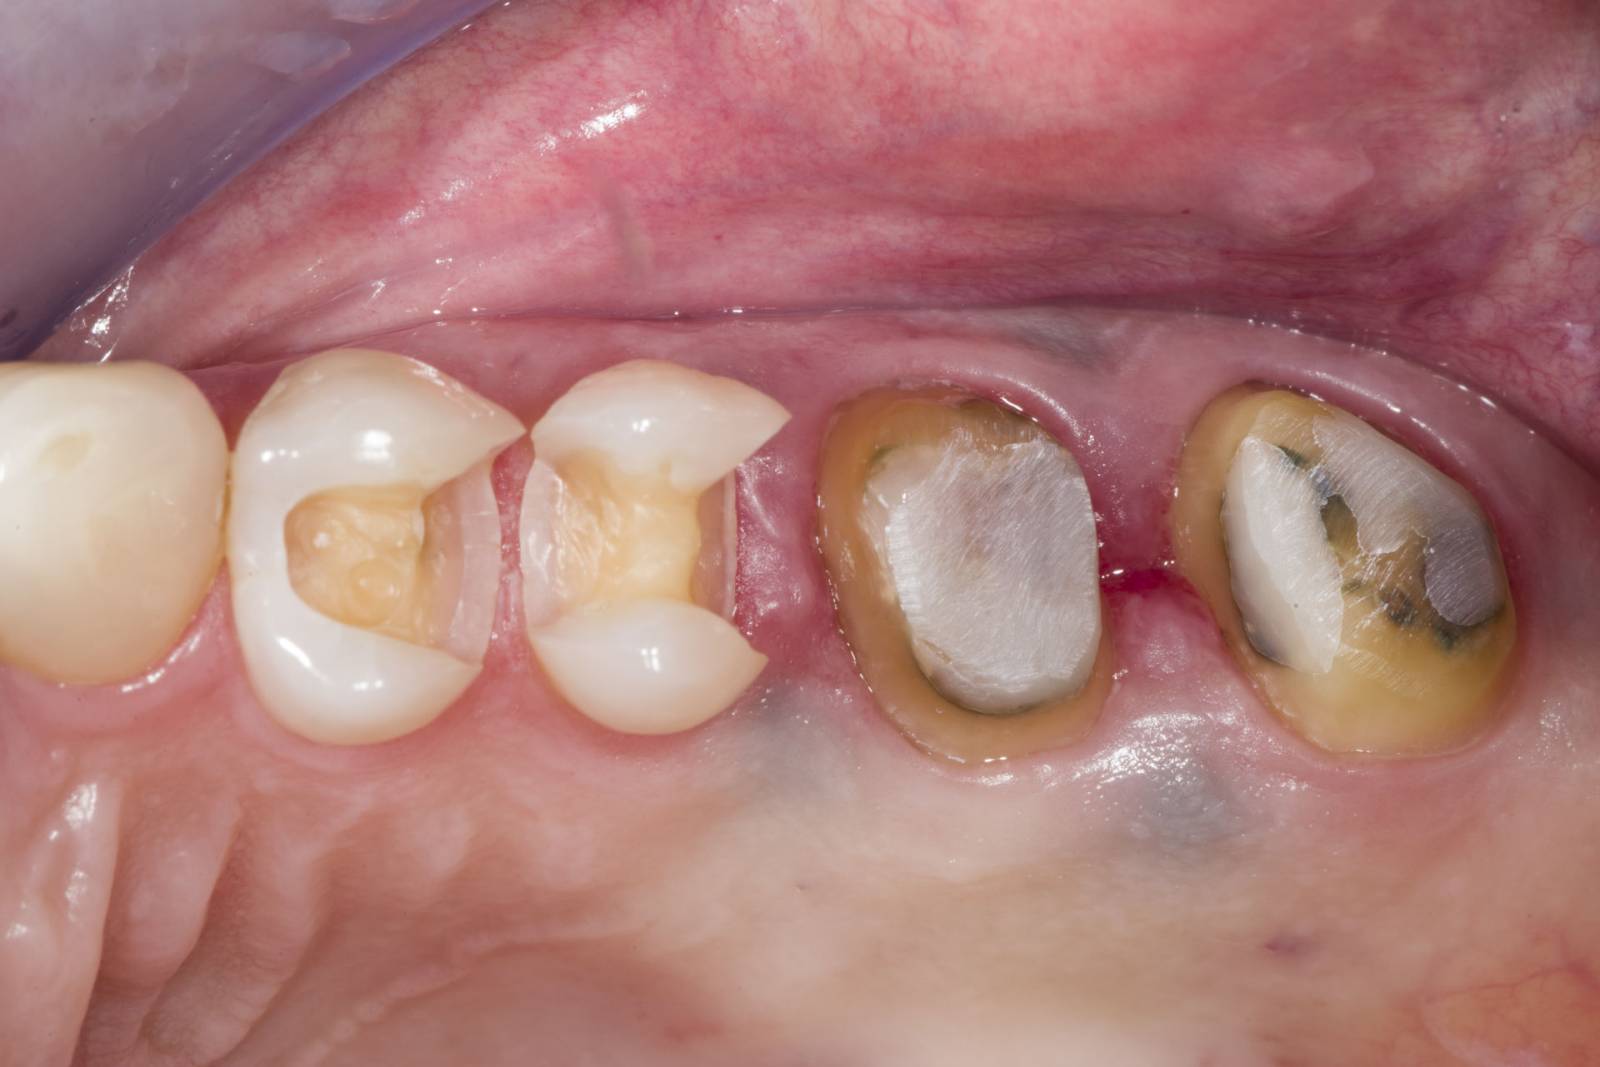

Restoration of MIH teeth with CEREC Tessera

A CEREC Tessera crown

Initial situation of the patient:

The patient presented with increasing temperature sensitivity at her six-year molars. The anamnesis did not reveal any evidence of a drug-associated or disease-associated enamel malformation. The mother’s pregnancy was without complications. Clinical examination revealed extensive substance loss and hypomineralised enamel encompassing the entire clinical crowns of teeth 16 and 26. Furthermore, the left central incisor and both mandibular first molars were affected by hypomineralisations. Tooth 21 had no cavitation and showed no hypersensitivity. The lower first molars had small cavitations with hypersensitivity. Based on these findings diagnosis was molar-incisor-hypomineralisation (MIH). According to the MIH-Treatment-Need-Index [Bekes & Steffen 2016] teeth 16 and 26 were assigned to Score 4c requiring full crown coverage. Tooth 21 was assigned to Score 1 and was left as it was at the request of the mother and the patient herself. Teeth 36 and 46 were assigned Score 4b and were restored with direct composite restorations.

At this point, the maxillary molars were not yet fully erupted. Therefore, these teeth were initially restored with direct composite restorations to await complete tooth eruption. At the age of 11, tooth 16 and 26 had erupted completely allowing for full crown restorations.

Dr. Sebastian Soliman

Würzburg, Germany